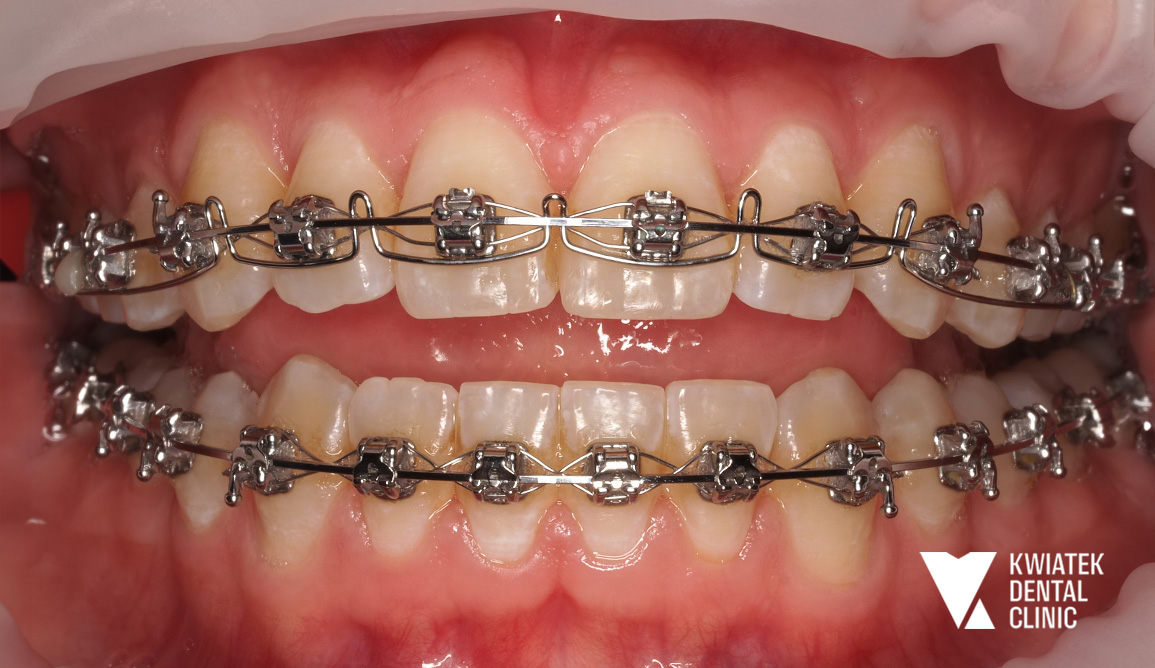

PO

Leczenie rozpoczęto od profesjonalnej higienizacji jamy ustnej. Podczas wizyty stwierdzono znaczne nagromadzenie płytki bakteryjnej oraz kamienia nazębnego w przestrzeniach międzyzębowych, dlatego przeprowadzono dokładny instruktaż higieny oraz zalecono odpowiednie preparaty remineralizujące. Następnie wykonano chirurgiczne usunięcie zębów mądrości. Kluczowym etapem terapii było zastosowanie systemu Beneslider. Na podniebieniu wprowadzono dwa miniimplanty ortodontyczne o wymiarach 2.0/11 mm w znieczuleniu nasiękowym. Na zębach 16 i 26 osadzono pierścienie, a następnie zamontowano aparat dystalizujący umożliwiający przesunięcie zębów trzonowych do tyłu i uzyskanie przestrzeni w łuku. Po uzyskaniu odpowiednich warunków przestrzennych rozpoczęto leczenie aparatem stałym cienkołukowym zamkami samoligaturującymi. Aparat założono w obu łukach zębowych, a Pacjent otrzymał szczegółowy instruktaż higieny oraz zestaw ortodontyczny do codziennej pielęgnacji. W kolejnych miesiącach regularnie wykonywano wizyty kontrolne, podczas których aktywowano aparat, stosowano łuki ortodontyczne o różnej sztywności oraz elementy dodatkowe. W trakcie leczenia przeprowadzono także leczenie zachowawcze z użyciem materiałów kompozytowych w koferdamie i pod kontrolą mikroskopu. Równolegle wykonywano okresowe higienizacje oraz kontrolowano stan jamy ustnej, aby utrzymać zdrowe środowisko podczas terapii ortodontycznej.

Po zakończeniu leczenia zdjęto aparaty stałe z obu łuków zębowych, oczyszczono powierzchnie zębów z pozostałości kleju i wykonano dokumentację fotograficzną efektów terapii. Dla utrwalenia osiągniętych rezultatów zastosowano retencję w postaci stałego retainera oraz retainerów ruchomych dla obu łuków zębowych

Uzyskano prawidłowe ustawienie zębów w łukach, korektę zgryzu krzyżowego, właściwą relację zgryzową oraz harmonijną estetykę uśmiechu. Metamorfoza pokazuje, jak dzięki dokładnej diagnostyce, nowoczesnym technikom ortodontycznym oraz konsekwentnemu prowadzeniu leczenia można osiągnąć stabilny i naturalny efekt bez konieczności usuwania zębów przedtrzonowych.